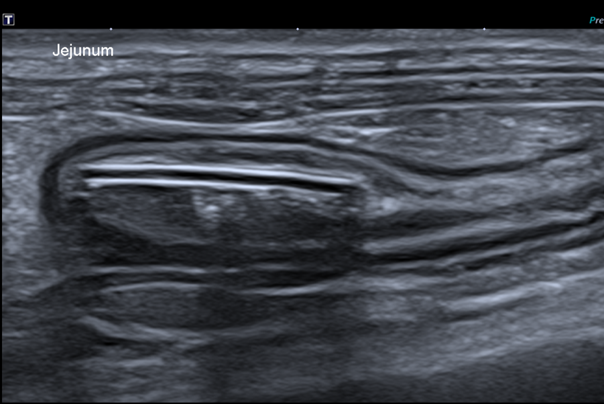

Échographie abdominale : visualisation d’un corps étranger dans le jéjunum

L’échographie offre également la possibilité de préciser de nombreux éléments :

• Visualisation de corps étrangers non radio-opaque, notamment des corps étrangers linéaires (avec plicature des anses).

• Distinction entre une obstruction liée à un corps étranger et tout autre type d’obstruction ; notamment une masse obstructive, ou une intussusception.

• L’intussusception peut également être secondaire : avec un péristaltisme augmenté et une obstruction mécanique, une anse peut s’invaginer dans une autre. L’aspect échographique est caractéristique, avec la visualisation d’une zone à double paroi digestive (intusseptum et intussuscipiens), à bien visualiser dans tous les plans pour éviter toute erreur d’interprétation.

• État de la paroi gastrique ou intestinale : épaississement, perte localisée de la structure en couches, ulcération voire perforation. Utilisation du Doppler permet d’évaluer la viabilité pariétale du segment intestinal touché.